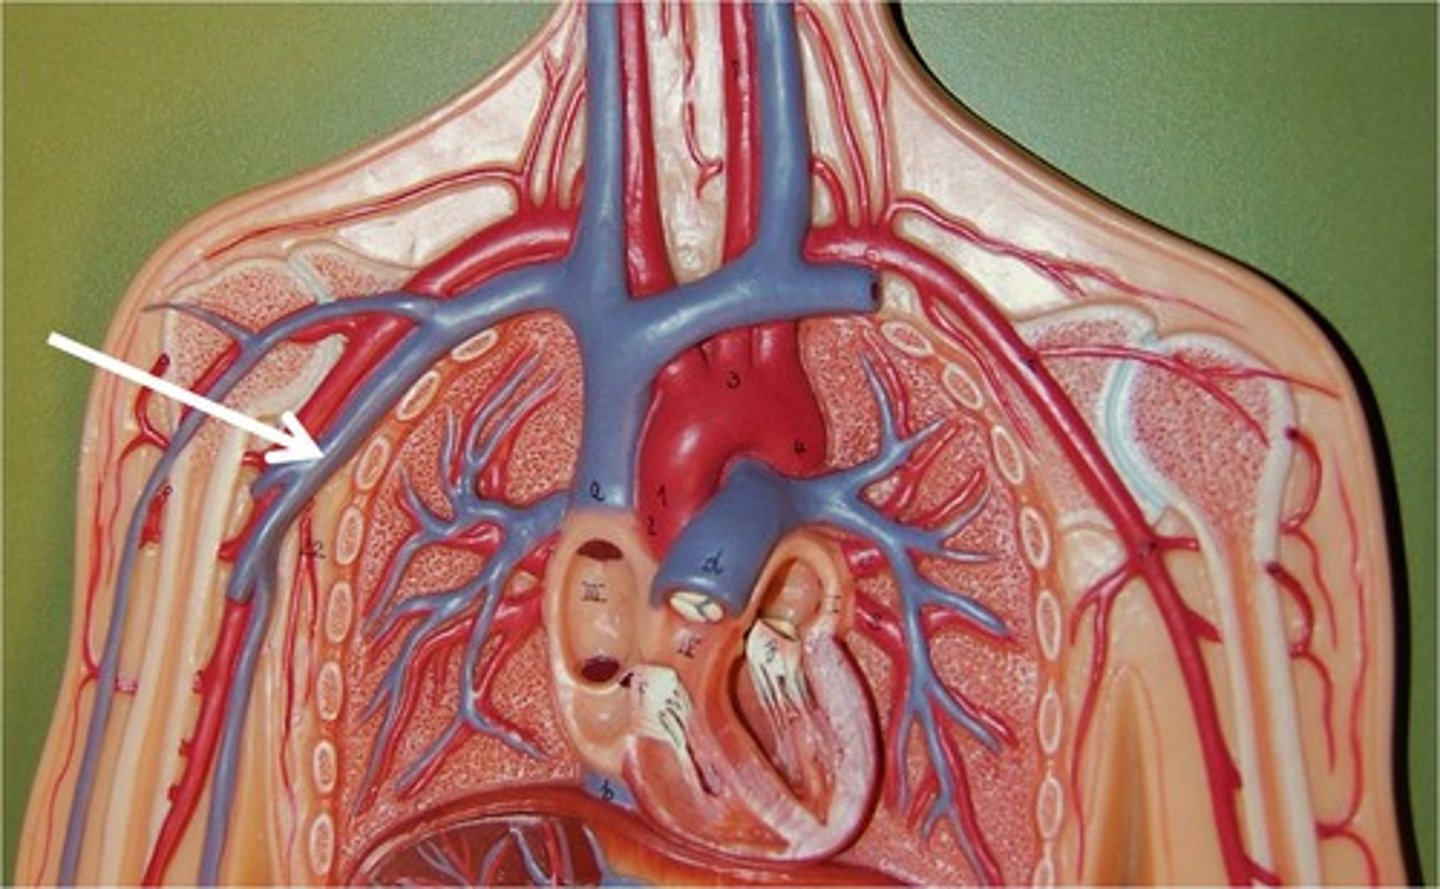

ascending aorta

branches include right and left coronary arteries

right coronary artery

left coronary artery

brachiocephalic artery

feeds right common carotid artery and right subclavian artery

aortic arch

feeds brachiocephalic artery, right and left common carotid arteries, right and left subclavian arteries

axillary artery

flows into axilla, lateral chest, and shoulder joint

brachiocephalic vein

subclavian vein

superior vena cava

axillary vein